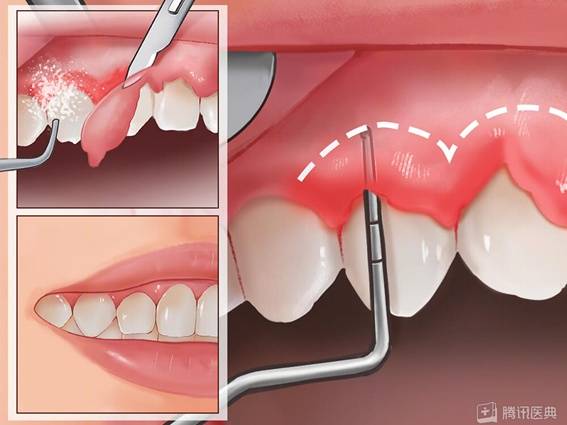

口腔卫生情况差,重度牙结石

牙龈红肿发炎严重

牙龈炎症持续发展,牙龈与牙齿分离形成牙周袋,深达10mm,里面藏污纳垢,还有大量结石……

经过多次牙周序列治疗,即全口洁治(洗牙)、龈下刮治、松牙固定术等,最终陈教授成功为她保住了所有牙齿。

比如,如果孕期得了牙周疾病,推荐在孕中期进行必要的牙周干预,如洗牙、脓肿引流、溃疡性牙龈炎的上药冲洗等。